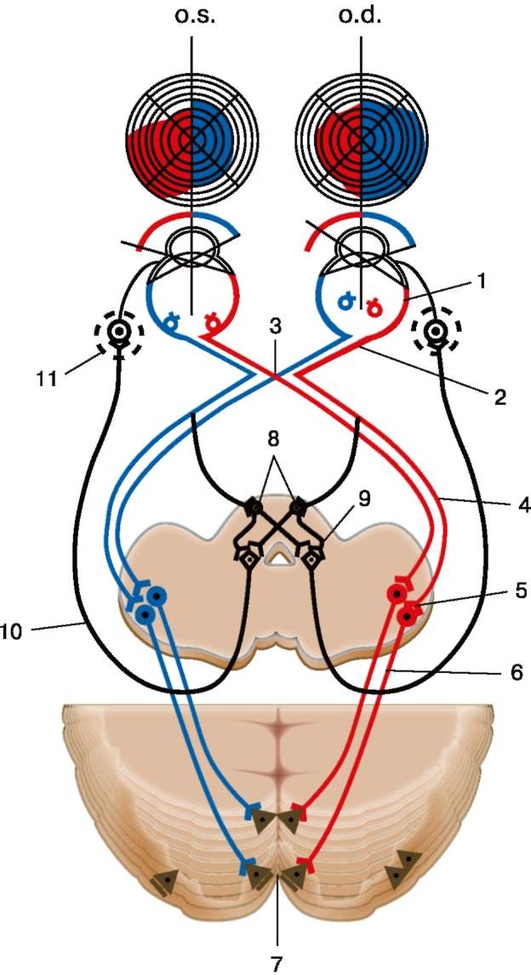

Рис. 2.1. Путь зрительных импульсов: 1 - глаз; 2 - зрительный нерв; 3 - неполный перекрест зрительных нервов (хиазма); 4 - зрительный тракт; 5 - наружное коленчатое тело; 6 - зрительная лучистость; 7 - первичная зрительная кора

Рис. 7.1. Зрительный анализатор и рефлекторная дуга зрачкового рефлекса: 1 - сетчатка глаза; 2 - зрительный нерв; 3 - хиазма; 4 - зрительный тракт; 5 - клетки наружного коленчатого тела; 6 - зрительная лучистость (пучок Грациоле); 7 - корковая проекционная зрительная зона - шпорная борозда; 8 - переднее двухолмие; 9 - ядра глазодвигательного (III) нерва; 10 - вегетативная часть глазодвигательного (III) нерва; 11 - ресничный узел